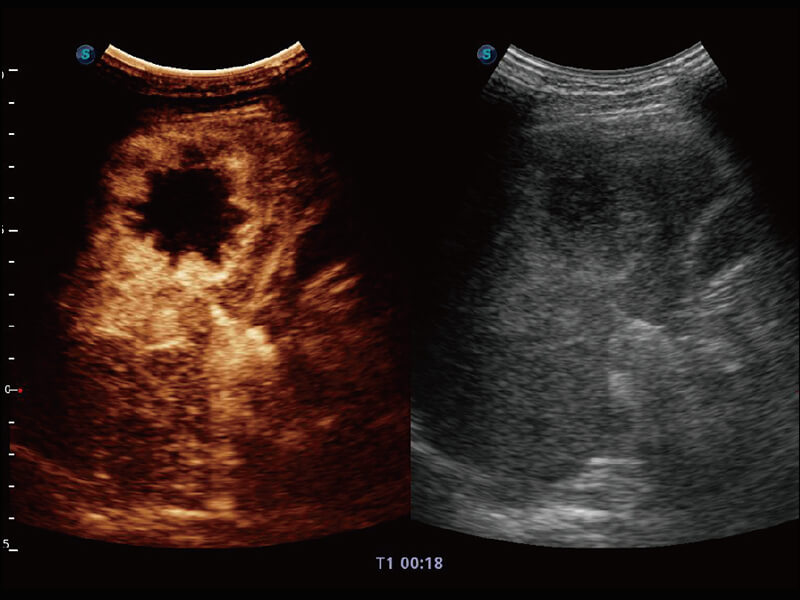

S60探头工艺,从前端信号处理每一个环节采集无损声学数据,真实还原组织原貌,再现解剖细节。